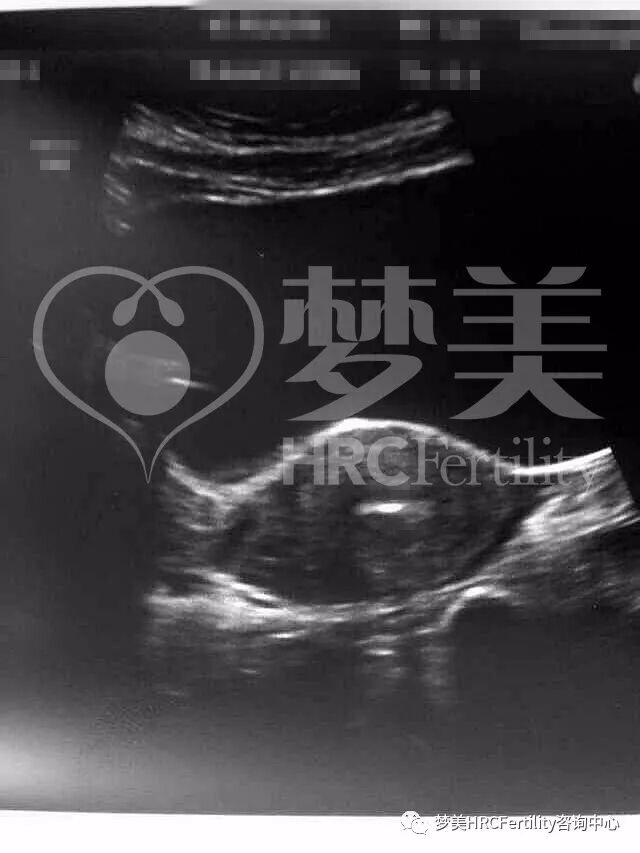

随后的B超检查,我们可以清晰看到囊胚已顺利着床开始发育!

(图上为女方B超显示成功怀孕图)